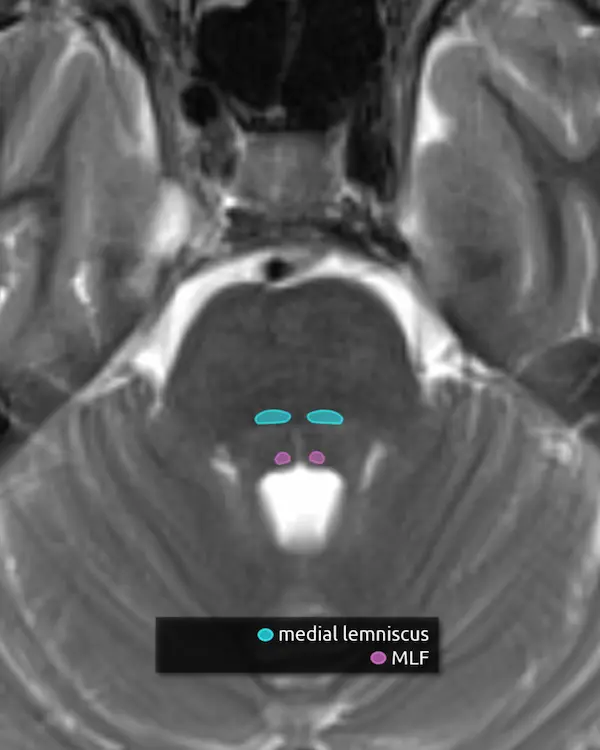

1. Pyramids

2. Inferior cerebellar peduncles

3. Medial lemniscus

4. Medial longitudinal fasciculus (MLF)

5. Spinal nucleus of the trigeminal nerve (CN V)

6. Solitary nucleus

5. Vestibular nuclei (CN VIII)

The vestibular nuclei are a complex of four cell groups located mostly in the dorsal medulla with some extension to the lower pons. The receive information from the inner ear and are responsible for balance, posture, and eye movement in response to head motion.

6. Cochlear nucleus (CN VIII)

The cochlear nuclei are a complex of two cell groups located in the dorsal medulla. They receive information from the inner ear and are responsible for hearing.

2. Spinocerebellar tracts